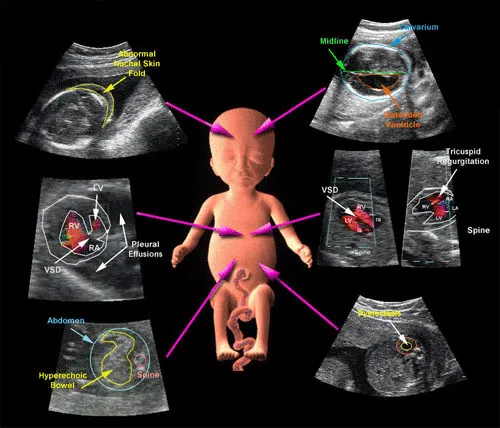

اکوکاردیوگرافی جنینی روشی است برای بررسی ساختار و عملکرد قلب جنین، که معمولاً بین هفتههای 18 تا 24 بارداری انجام میشود. برخلاف سونوگرافیهای معمولی، این روش بهطور اختصاصی قلب و عروق بزرگ را هدف قرار میدهد. اهمیت این روش در آن است که بسیاری از بیماریهای مادرزادی قلبی ممکن است در بدو تولد بدون علامت باشند اما در صورت تشخیص زودهنگام، میتوان اقدامات درمانی مناسب را پیش از زایمان یا بلافاصله پس از تولد برنامهریزی کرد.

برخی از اختلالاتی که به کمک اکوکاردیوگرافی جنینی قابل تشخیص هستند شامل نقص تیغه بینبطنی، تترالوژی فالوت، نارسایی دریچهای، تنگی یا انسداد شریان ریوی، و آریتمیهای جنینی میباشند. در نتیجه، تشخیص بهموقع از طریق این روش میتواند نقش نجاتدهندهای در زندگی نوزاد ایفا کند.

اکوکاردیوگرافی جنینی میتواند بهصورت ترانسابدومینال (از طریق شکم مادر) یا ترانسواژینال (در موارد خاص) انجام شود. ابزارهایی مانند پروبهای سونوگرافی با فرکانس بالا، قابلیت تصویربرداری داپلر، و تکنیکهای سهبعدی (3D) و چهاربعدی (4D) در تشخیص دقیقتر کمک شایانی میکنند.

تصاویر با وضوح بالا از حفرههای قلب، جریان خون درون عروق، و ریتم قلبی جنین، پزشک را قادر میسازند تا هرگونه ناهنجاری در مراحل اولیه شناسایی شود. همچنین در برخی موارد خاص، اکوکاردیوگرافی ترانسواژینال در سهماهه اول بارداری برای بررسی دقیقتر مورد استفاده قرار میگیرد، بهویژه زمانی که شک به ناهنجاری شدید وجود دارد یا سابقه خانوادگی بیماریهای ژنتیکی قلبی مطرح است.